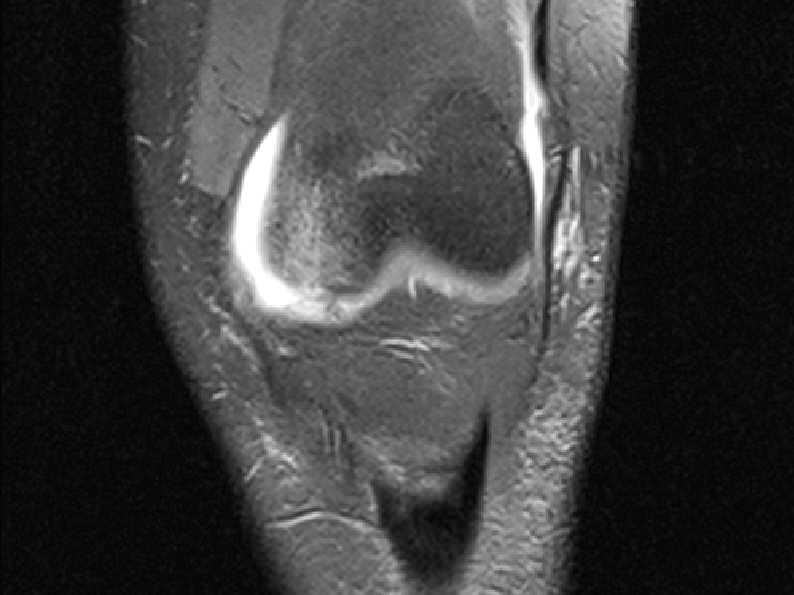

Case I - 19 year male, left knee injured by falling from stairs. Full knee dislocation has occurred. The dislocated limb was reposed and immobilized with brace. No surgery was applied. - MRI – ACL, LCL, PLC injury was diagnosed - neurology – complete CPN palsy.

• Mrt / ro